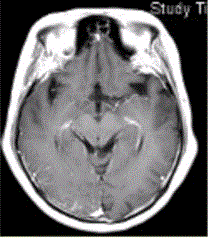

问题 女性,62岁,乳腺癌病史,头颅MR增强检查显示如下图,可能的诊断为

选项 A.脑结核 B.硬脑膜转移 C.柔脑膜转移 D.脑膜炎 E.脑膜肉芽肿

答案 C